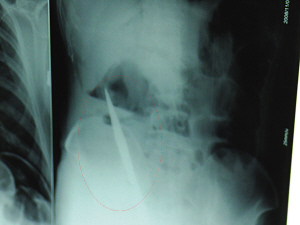

X光片上,尖刀清晰可見。

從男子體內(nèi)取出的尖刀足足有19厘米長。

6日上午,記者在徐州礦務(wù)集團(tuán)總醫(yī)院重癥監(jiān)護(hù)室見到了這名男子,目前他雖然已經(jīng)恢復(fù)了意識(shí),但還不能開口說話,需要呼吸機(jī)輔助呼吸。據(jù)醫(yī)生介紹,4日中午12時(shí)左右,這名男子因服毒輕生被緊急送到醫(yī)院進(jìn)行搶救,之前,這名男子已經(jīng)在當(dāng)?shù)剜l(xiāng)鎮(zhèn)醫(yī)院進(jìn)行了近20小時(shí)的治療,但效果不佳。“病人被轉(zhuǎn)院到礦總院時(shí)已神志不清,血壓極低,處于休克狀態(tài)。”救護(hù)人員給男子洗胃、初步處理以后,發(fā)現(xiàn)男子呼吸急促,于是趕緊給他拍片檢查。結(jié)果讓所有的醫(yī)生大吃一驚,竟有一把尖狀異物橫在該男子腹腔內(nèi)!當(dāng)天下午5時(shí)30分,輕生男子被推上了手術(shù)臺(tái)。經(jīng)過40多分鐘的手術(shù),該男子腹腔被打開,手術(shù)醫(yī)生發(fā)現(xiàn),男子體內(nèi)的金屬狀異物竟然是一把長19厘米的尖刀!